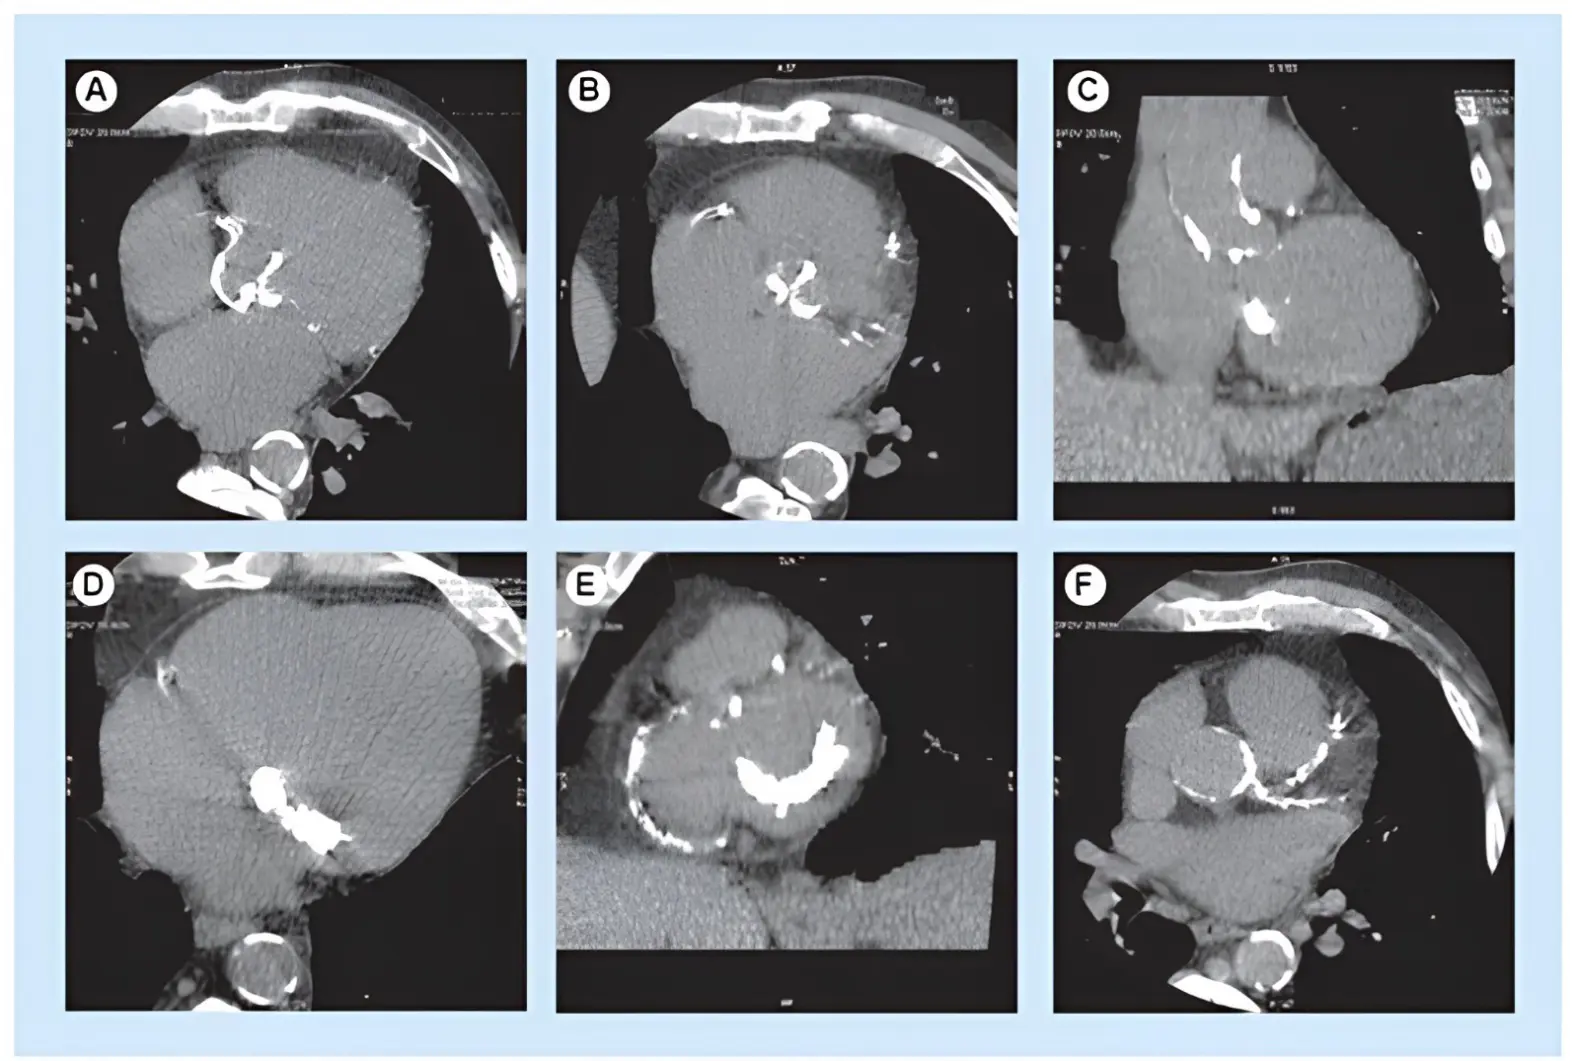

Cardiac computed tomography (CT) has become an essential tool in the evaluation of native aortic stenosis (AS), offering critical insights that complement and often enhance traditional echocardiography. One of its key applications is aortic valve calcium scoring, where the Agatston method is used on non contrast, electrocardiogram (ECG)-gated scans to quantify the extent of calcification (Figure 2). Thresholds of >1300 Agatston units (AU) in women and >2000 AU in men are typically used to define severe AS [36,37]. This approach is particularly valuable when echocardiographic findings, such as aortic valve area (AVA) and pressure gradients, are discordant. In such cases, CT calcium scoring has demonstrated good diagnostic performance, with a sensitivity of 82% and specificity of 78% for detecting severe AS [37,38]. Moreover, higher calcium scores are strongly associated with disease progression and worse outcomes, with a hazard ratio of 2.11 for mortality [36,38].

Figure 2. Non-enhanced CT of severe aortic valve calcification. Heavy aortic valve calcification burden seen in (A) the axial and (B) reformatted plane of the aortic valve, associated with (C) severe thoracic aorta, (D,E) mitral valve and (E,F) coronary artery calcifications.